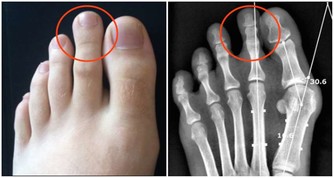

所謂內源性尿酸,是人體代謝過程中自行產生的。當體內嘌呤代謝紊亂,或惡性腫瘤等疾病患者因放化療使腫瘤細胞大量破壞分解,也會導致血尿酸水平的急劇上升。

此外,正常情況下,約有2/3 的血尿酸通過腎臟排出人體。

當患腎臟疾病導致腎臟功能下降時,尿酸會慢慢在體內堆積,同樣可使血尿酸濃度上升,導致痛風。